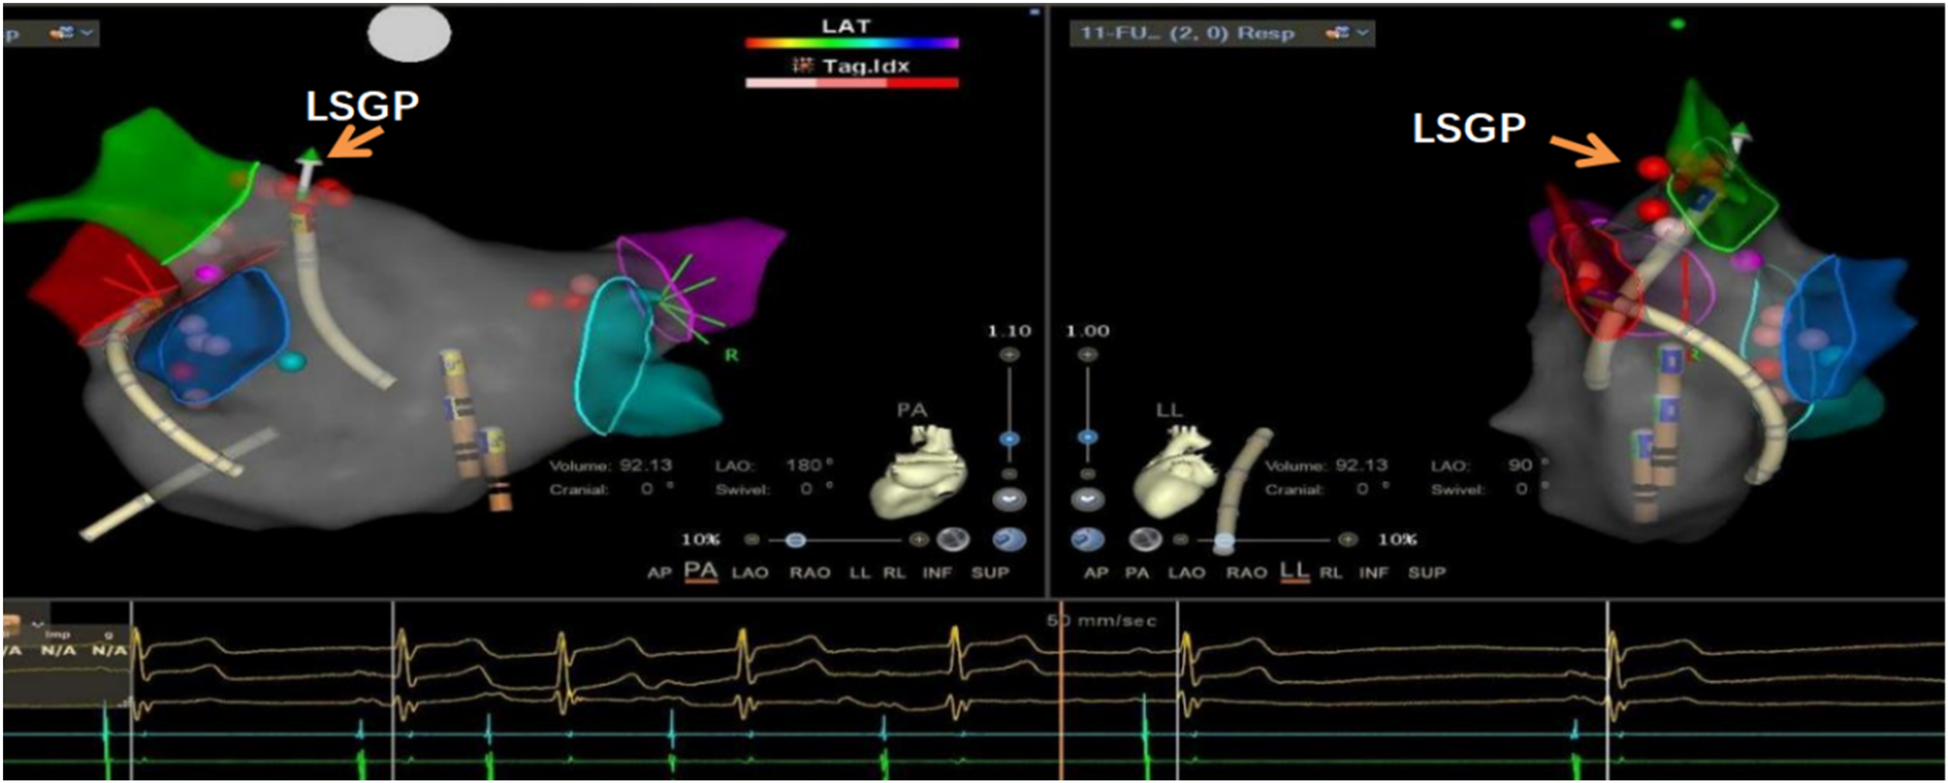

This study utilized the Carto electrophysiological navigation system (CARTO3, FG-5400-00C, USA) for cardiac modeling and ablation. Under intracardiac ultrasound guidance, a right atrial model was established, and three-dimensional fossa ovalis positioning was performed. Zero-ray transseptal puncture was carried out, and the SL1 sheath was advanced into the left atrium, as shown in Figure 2. Using the left atrial model for guidance, GP ablation was performed based on anatomical localization (temperature-controlled at 43°C, 40-watt discharge, with cold saline irrigation). During GP ablation, vagal responses including significant sinus bradycardia, sinus arrest, and atrioventricular block were observed, as shown in Figure 3. Ablation sites were marked, and ablated around these points reinforcely until vagal responses were no longer elicited. GP ablation was sequentially performed in the left superior GP (LSGP), left inferior GP (LIGP), right superior GP (RSGP), and right inferior GP (RIGP), as illustrated in Figure 2B. If five consecutive ablations within a GP region failed to induce any vagal response, the procedure proceeded to the next GP region. In most cases (80%), if the sinus rhythm gradually increased to approximately 90 beats per minute during ablation of the right superior pulmonary vein GP, ablation in that area was terminated at that point, as shown in Figure 4. The increase in sinus rhythm, disappearance of vagal reflexes, and completion of anatomical ablation signified the end of the procedure. Electrophysiological studies (EPS) demonstrated that the sinoatrial node recovery time and AV Wenckebach point were significantly shortened postoperatively compared to preoperative values, as shown in Figure 5.

Figure 3. Significant sinus bradycardia and first-degree atrioventricular block after ablation of the left upper ganglionated plexus (LSGP) of the left atrium, indicating that this was the target ablation site.